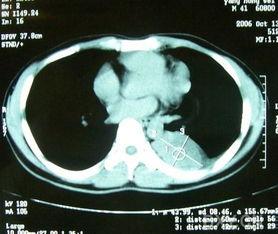

在很久以前,医生们只能通过X光片来观察肿瘤。那时的照片,黑白的,模糊的,就像是一幅抽象画。随着科技的发展,CT(计算机断层扫描)和MRI(磁共振成像)等先进技术逐渐取代了X光,使得肿瘤照片更加清晰、立体。

肿瘤照片对于医生来说,就像是一份密码。他们需要仔细观察照片中的每一个细节,从肿瘤的大小、形状、边界到周围组织的反应,这些都是判断肿瘤性质和制定治疗方案的重要依据。

还记得那些黑白模糊的X光片吗?如今,肿瘤照片已经进入了高清时代。CT和MRI等设备能够捕捉到更加细腻的图像,使得医生能够更加准确地判断肿瘤的位置和大小。

肿瘤照片不仅仅用于诊断,它们还在治疗过程中发挥着重要作用。医生可以通过肿瘤照片来观察治疗效果,调整治疗方案。例如,在放疗过程中,医生会定期拍摄肿瘤照片,以确保放疗的精准度。